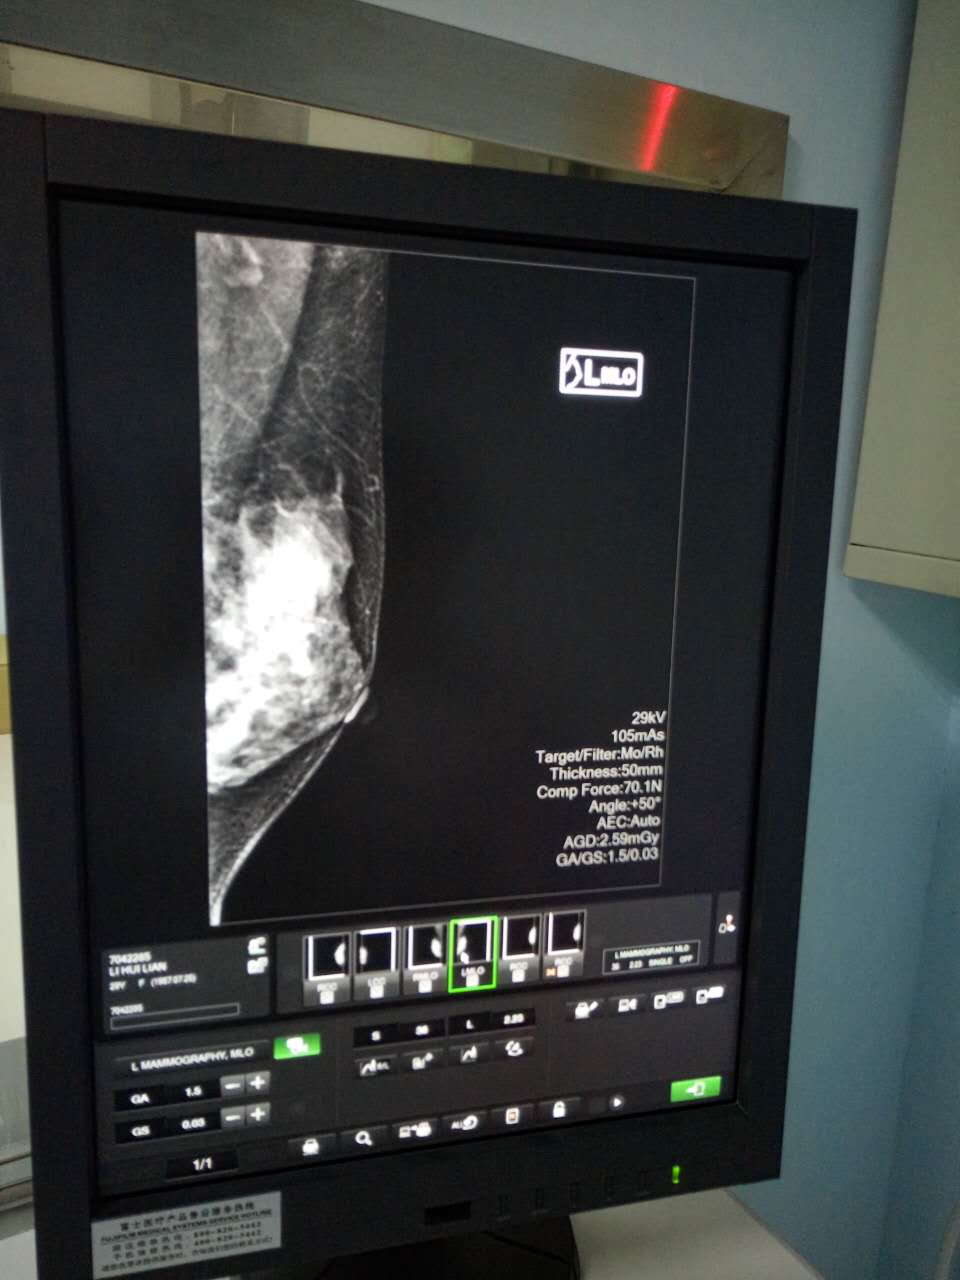

继今年6月14日海南西部中心医院肿瘤外科运用美国安珂乳腺真空旋切系统,开展首例乳腺肿瘤旋切手术获得成功后,7月27日,该院第一台数字化乳腺X线机(又称乳腺钼靶)在医院东病区(新区)投入使用,不仅填补了该院乳腺X线检查的空白,还由此形成了乳腺疾病的检查、治疗一条龙的格局。这对广大妇女同胞来说,无疑是一个振奋人心的消息。

据该院放射科主任、主任医师李岩介绍,乳腺钼靶是一种专门用于乳腺病变检查的设备,它通过低剂量软X线拍摄乳腺,能清晰显示乳腺各层组织,可以发现乳腺增生、各种良恶性肿廇及乳腺组织结构紊乱,可观察到小于0.1毫米的微小钙化点及钙化簇,对于临床不可触及的以微小钙化簇为唯一表现的早期乳腺癌,具有特征性的诊断意义。该检查具有全面、直观、操作简单、安全和费用低廉等特点,是目前早期乳腺癌筛查的有效手段。